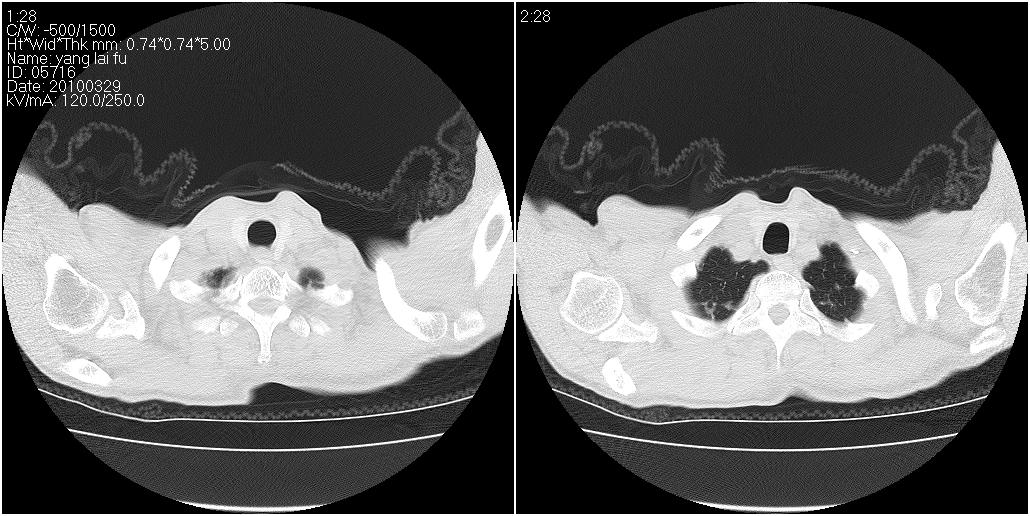

标题: CT25416:男性,70岁。胸片发现右下肺斑片状阴影 [打印本页]

标题: CT25416:男性,70岁。胸片发现右下肺斑片状阴影

以下是ct检查的情况:

考虑右肺下叶炎症可能性大?未除占位,建议增强。右下肺肺不张

右下胸壁皮下气肿。